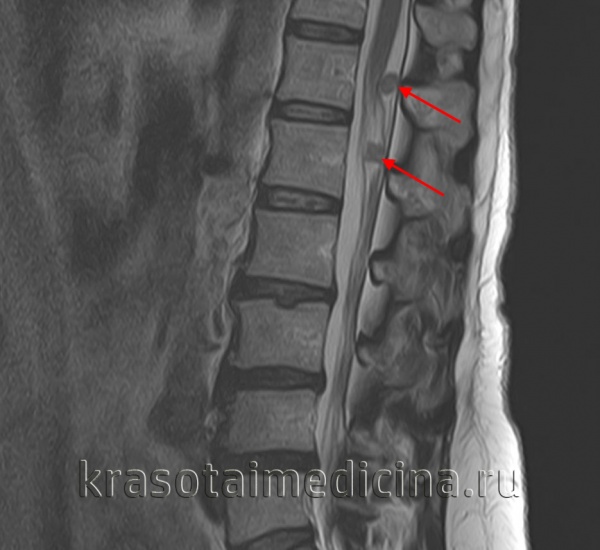

(Справа) MPT Т2ВИ, аксиальная проекция. Округлое образование с неоднородным сигналом, которое смещает общую сонную артерию кпереди. Внутренняя яремная вена смещена вместе с артерией. При сдавливании яремной вены ее идентификация может быть затруднена.

4. МРТ при шванноме симпатического ствола:

• Т2ВИ:

о Новообразование заднего отдела сонного пространства с сигналом промежуточной интенсивности (выше, чем у мышечной ткани)

о Если в толще опухоли имеются кисты, границы их обычно четкие, а сигнал - гиперинтенсивный

• Т1ВИ с КУ:

о Небольшие образования: однородное накопление контраста

о В крупных образованиях определяются не контрастируемые зоны кистозных изменений

(Слева) МРТ Т1ВИ FS с КУ, аксиальная проекция. В задних отделах подподъязычного сонного пространства расположено образование округлой формы. Шваннома симпатического ствола смещает и сонную артерию, и внутреннюю яремную вену кпереди. Одновременное смещение обоих сосудов сонного пространства весьма характерно для шванномы симпатического ствола.

(Справа) МРТ Т1ВИ FS c КУ, коронарная проекция. Шваннома симпатического ствола, расположенная в сонном пространстве. Опухоль неравномерно накапливает контрастное вещество. Участки кистозного перерождения в крупных шванномах встречаются достаточно часто.